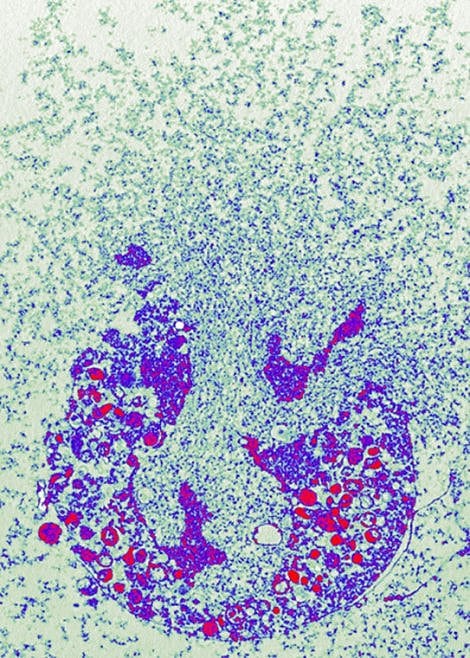

Bakterien ins Netz gegangen | Die farbige rasterelektronenmikroskopische Aufnahme zeigt stimulierte Neutrophile mit Netzen und darin gefangenen Shigellen (orange).

Im Netz gefangenes Shigella-Bakterium | Shigella-Bakterien sind hier neutrophilen Granulozyten in ihre NETs gegangen. Rasterelektronenmikroskopische Aufnahme.